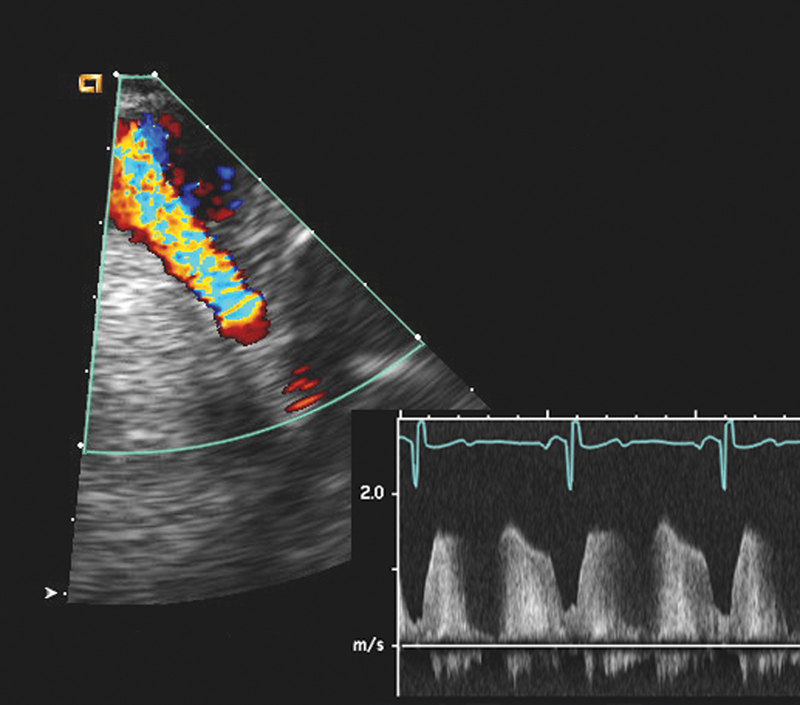

فحوصات تشخيصية لبعض امراض القلب والشرايين التاجية